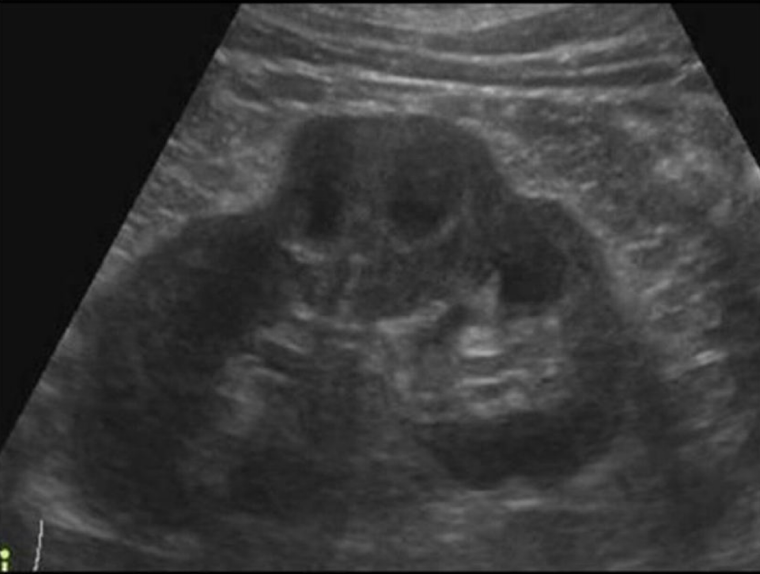

This type of congenital variant occurs when there is fusion of the kidneys.typically the fusion is of the lower poles

Horseshoe kidney

Which type of analomy is shown in this image→ ?